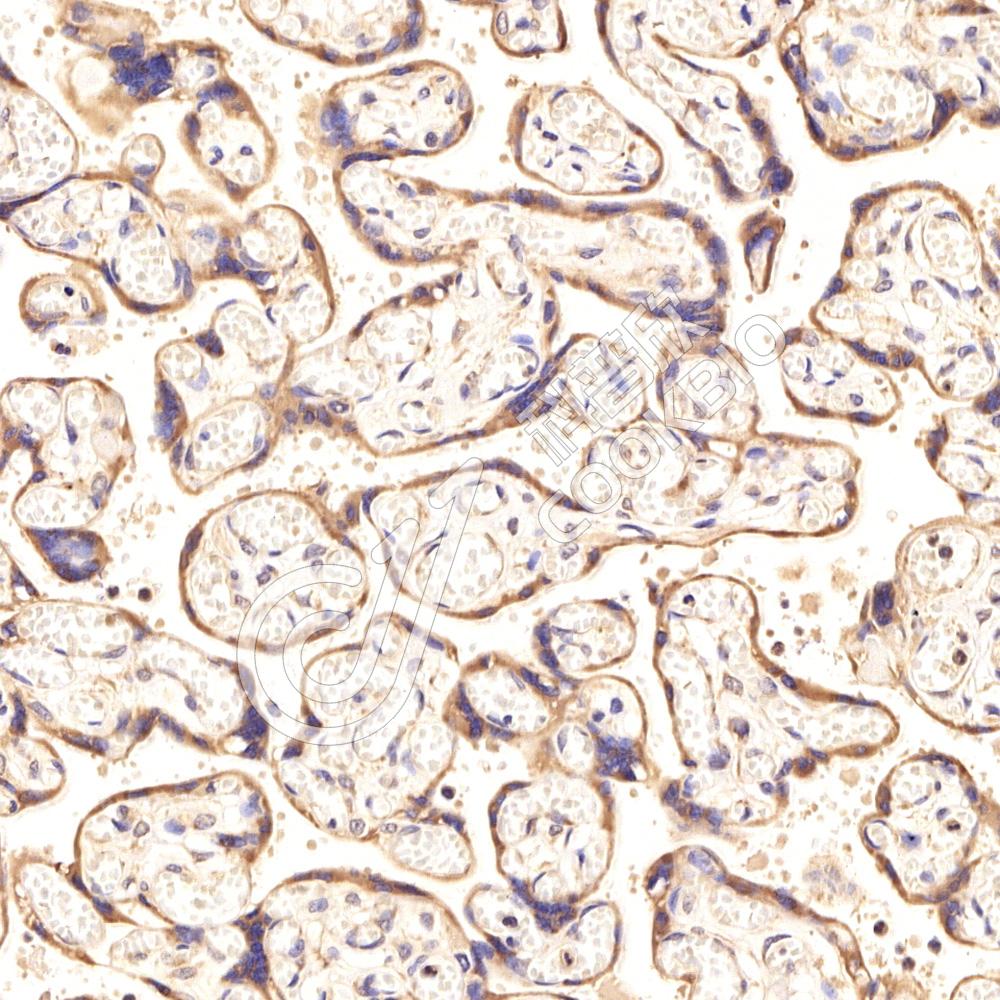

IHC检测PLA1A/NMD蛋白(货号 K1339567).

样品: 人胎盘, 4%多聚甲醛 (货号KSG1101) 固定12-24小时.

抗原修复: 柠檬酸抗原修复液(干粉, pH 6.0) (KSG1201), 98℃, 20分钟.

—抗: 1: 1800稀释, 4℃ 孵育过夜.

二抗: S-vision免疫组化多聚二抗(山羊抗兔),即用型 (货号KB3906), 室温孵育20分钟.